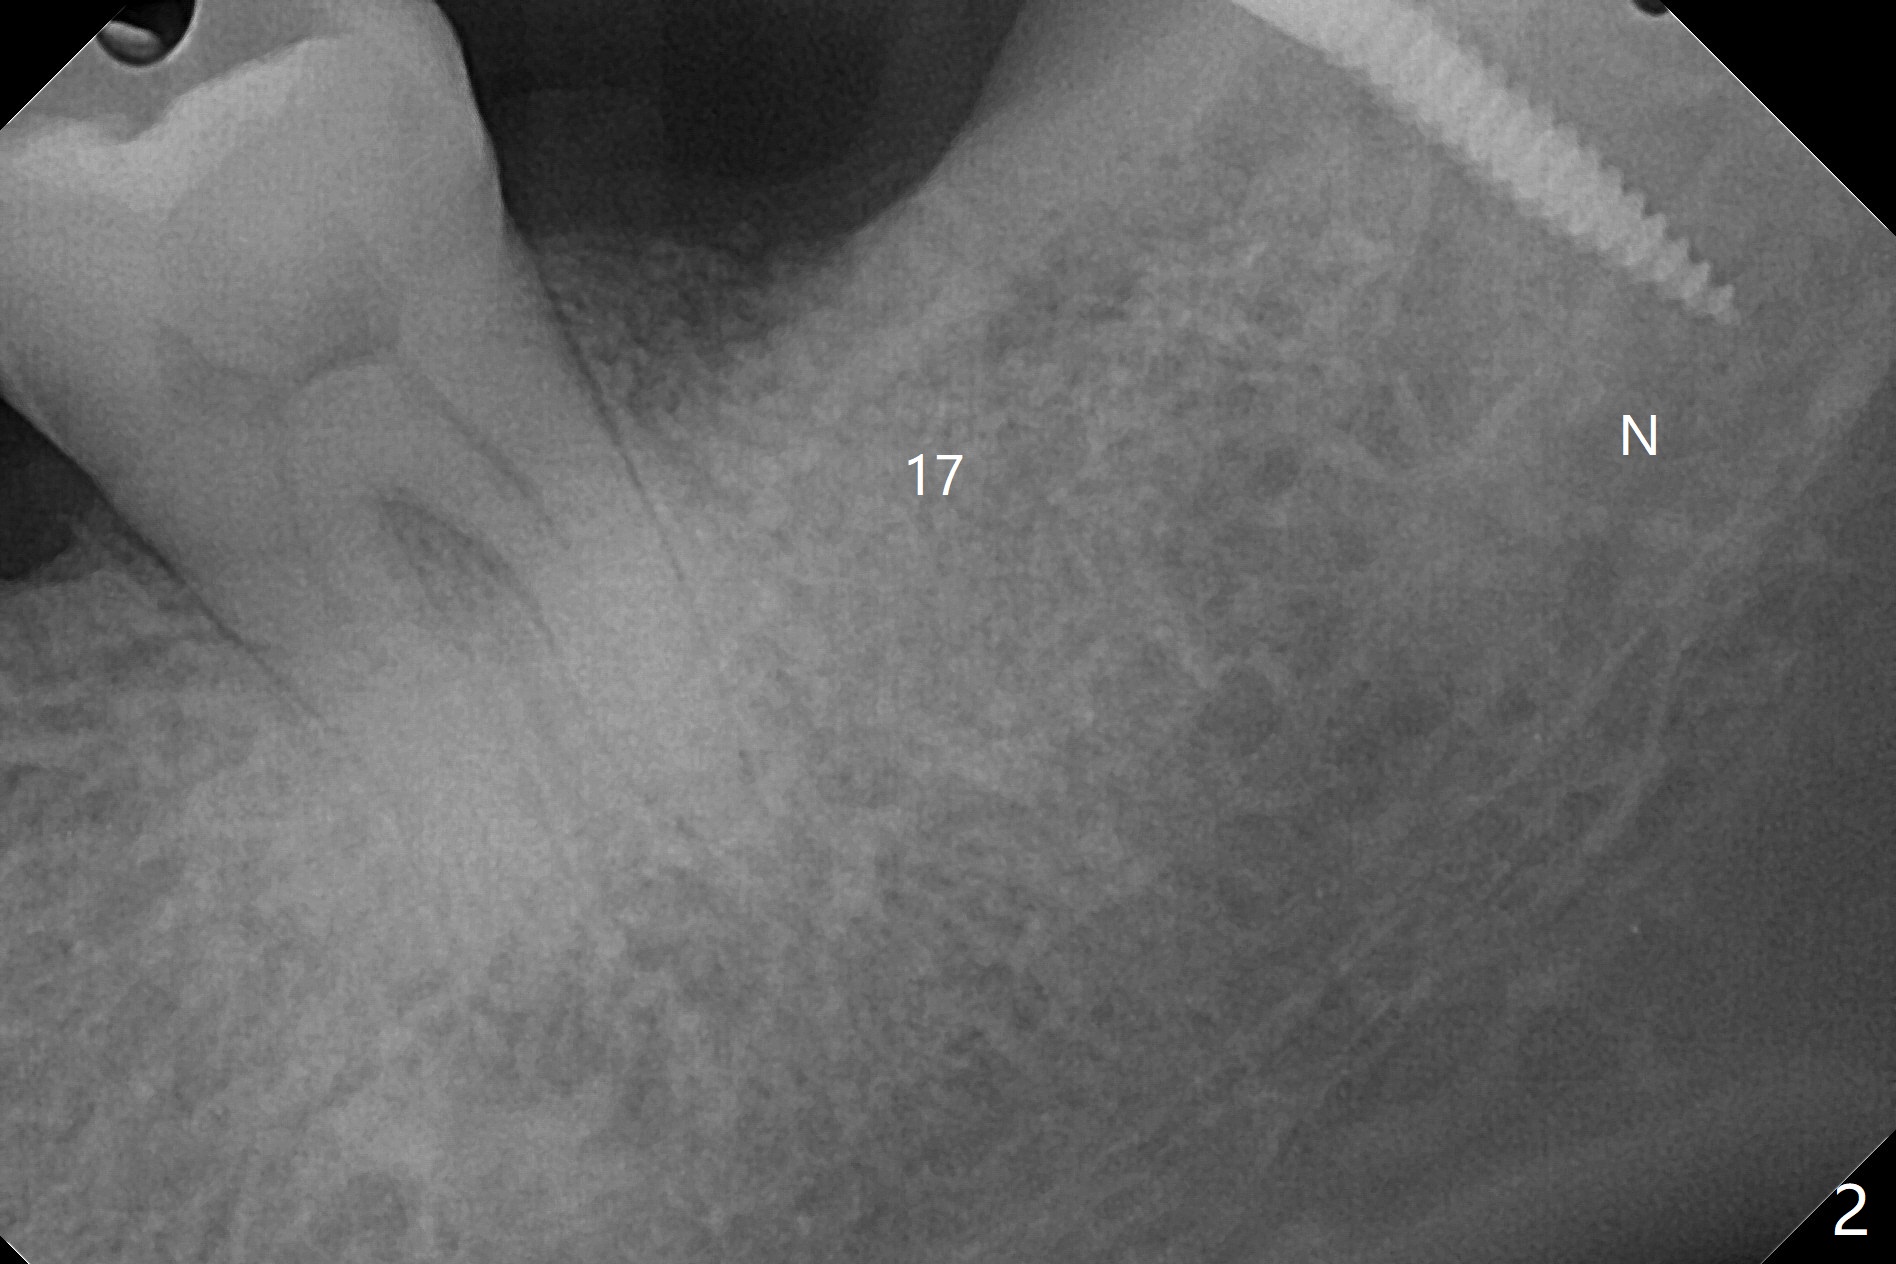

#17牙拔除植骨后1.5月(图一),准备在牙槽窝远中,即升支,种植一个抛锚,局麻下,首先不切开,钻洞,有些不放心,后来切开植入2x10(2)毫米一段式带球状基台植体(图二),植体根尖好像进入神经管(N)。CT显示植体却植入太接近舌侧骨板(图三:L),其实应该术前拍摄CT。由于18号牙同时扭转,安置磨牙圈(molar band),利用power chain进行牵拉以及矫正扭转(图四)。问题:升支抛锚种植位置对吗?power chain挂在抛锚上不稳定。